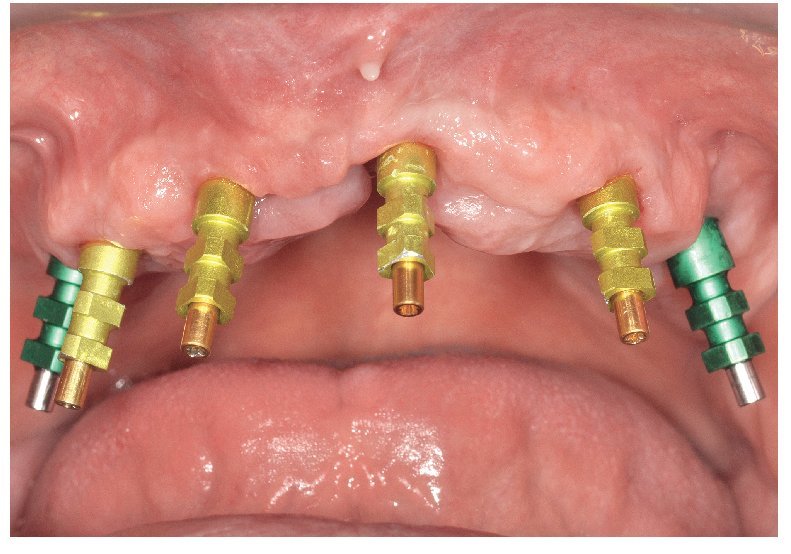

La intervención quirúrgica (figs. 63 y 64) se realizó bajo anestesia local y se trataron al mismo tiempo ambas arcadas dentarias. Durante la primera fase se insertaron seis implantes cónico-cilíndricos (SPI®CONTACT, Thommen Medical AG, Waldenburg, Suiza) en la arcada dentaria superior mediante un acceso sin colgajo. Para ello se utilizaron los pilares pertinentes para reposiciones de puente atornilladas oclusalmente (VarioMulti, Thommen Medical AG, Waldenburg, Suiza) (fig. 65). Tras la intervención quirúrgica se colocó en boca la prótesis provisional prefabricada a partir de los datos de planificación y tallada en las posiciones de implante y se unió a las cofias provisionales (fig. 66 y 67); para ello se utilizó un composite de fraguado dual. Mediante una prótesis provisional mucosoportada se pudo preservar la estructura gingival hasta el momento de la implantación, y con ello la relación correcta entre los maxilares superior e inferior. Para la arcada dentaria inferior se utilizaron implantes cilíndricos (Element, Thommen Medical AG) (figs. 68 y 69). En combinación con los pilares pertinentes para prótesis atornilladas, se procedió aquí de la misma manera que en el maxilar superior. Una vez se hubo alineado oclusalmente la prótesis provisional del maxilar inferior con respecto al superior, se fijó sobre las cofias provisionales (fig. 70); debido a la formación de colgajo no había sido posible la alineación sobre la mucosa. Este procedimiento permite preservar la dimensión oclusal vertical que se definió al principio del tratamiento. A continuación se repasan, se pulen y se envían a la clínica para su incorporación las prótesis provisionales, las cuales, por el contrario, se apoyan exclusivamente sobre los implantes (figs. 71 y 72). Allí tienen lugar el control radiológico y el rectificado oclusal (figs. 73 y 74).

Fig. 70. La prótesis provisional del maxilar inferior se une a los pilares; para ello se alinea a partir de la guía oclusal de la prótesis provisional del maxilar superior.